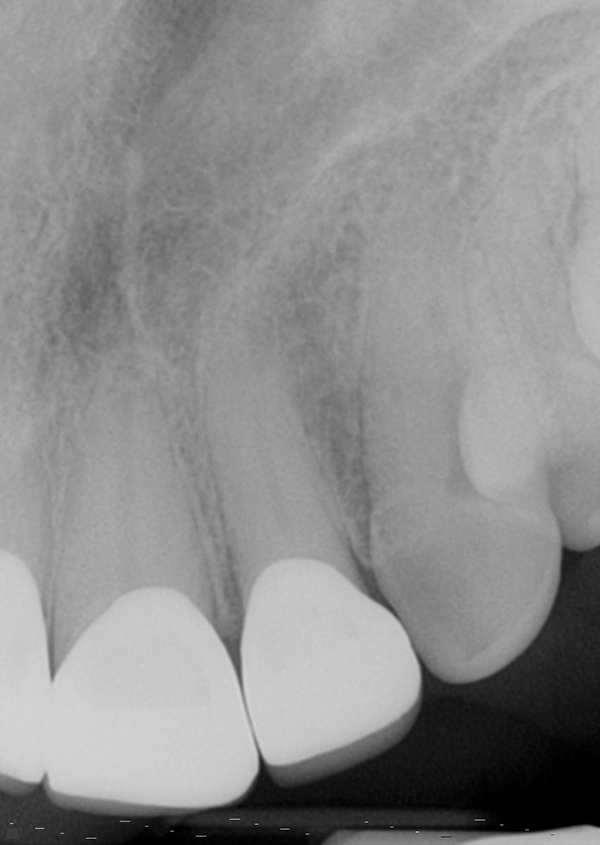

Fig 8. Final periapical radiographs of the restorations prior to delivery. The marginal integrity interproximally is evaluated to ensure adequate seating of restorations and closed margins.

Figure 8

Fig 9. Final periapical radiographs of the restorations prior to delivery. The marginal integrity interproximally is evaluated to ensure adequate seating of restorations and closed margins.

Figure 9

The restorations were delivered a few weeks later. Prior to cementation, marginal integrity of the restorations was reviewed. The author's protocol for approval of restorations for final delivery includes tactile and radiographic evaluation of the margins (Figure 8 and Figure 9). Once the restorations were approved for marginal integrity, occlusion, contacts, and esthetics, the process of isolation and cementation began. In this case, it was decided to cement the restorations with resin-modified glass-ionomer cement (RMGIC). The long-term stability of using RMGIC to cement zirconia-oxide restorations, especially for preparations of teeth demonstrating an adequate resistance and retention form, has been shown to be effective in preventing premature loss of restoration and microleakage.17